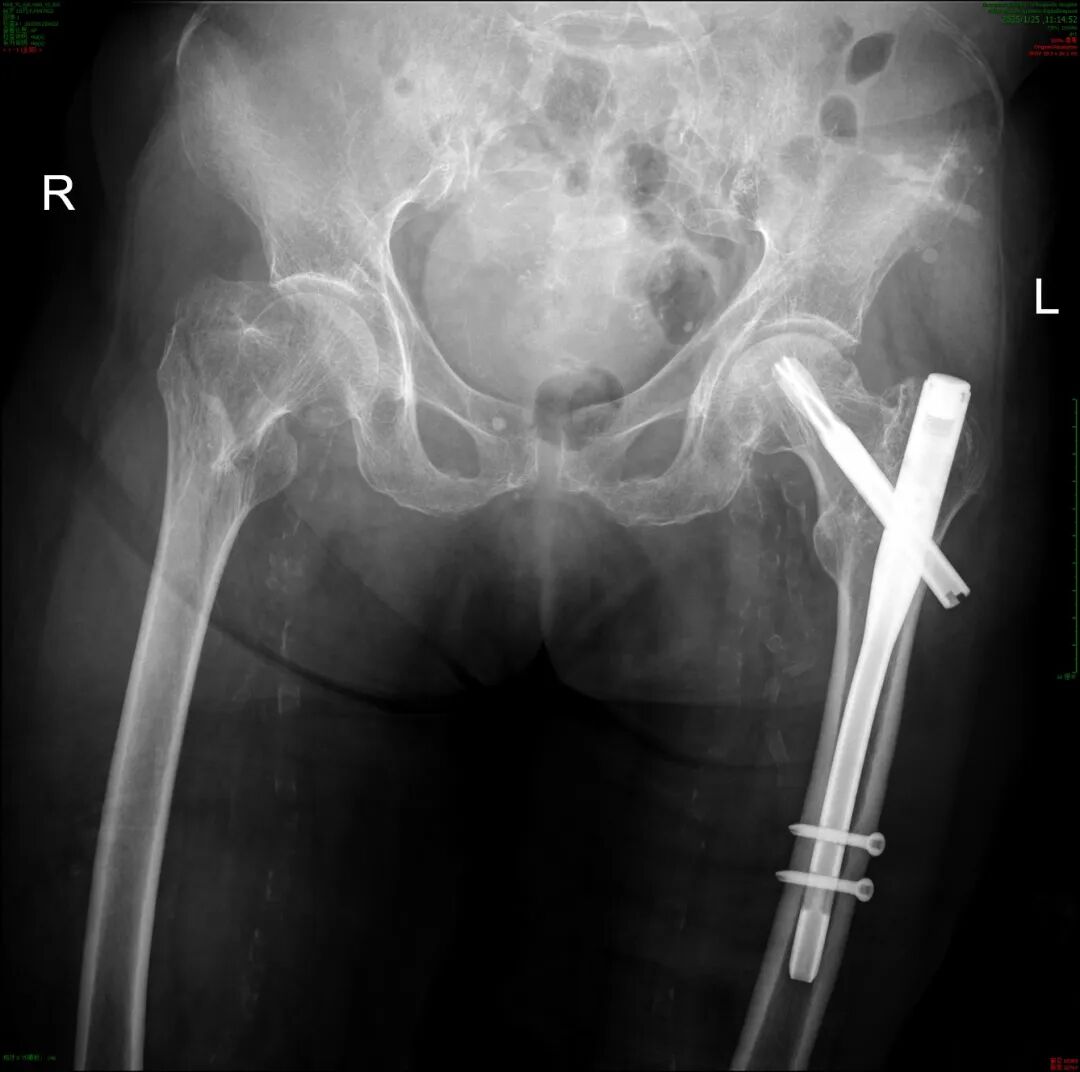

术前影像

我院急诊医生为张奶奶进行详细检查,诊断结果不容乐观 —— 粗隆间骨折。对于年轻人来说,骨折或许经过治疗便能较快恢复,但对于年近百岁的张奶奶,这无疑是一道生死难关。老人身体机能衰退,心肺功能薄弱,手术耐受性差,麻醉风险极高,术后恢复更是难上加难。

余新平副院长医疗团队随即为其开通了老年人髋部骨折绿色通道,并确定了右股骨粗隆间骨折闭合复位髓内钉内固定术的手术方案(InterTAN)。